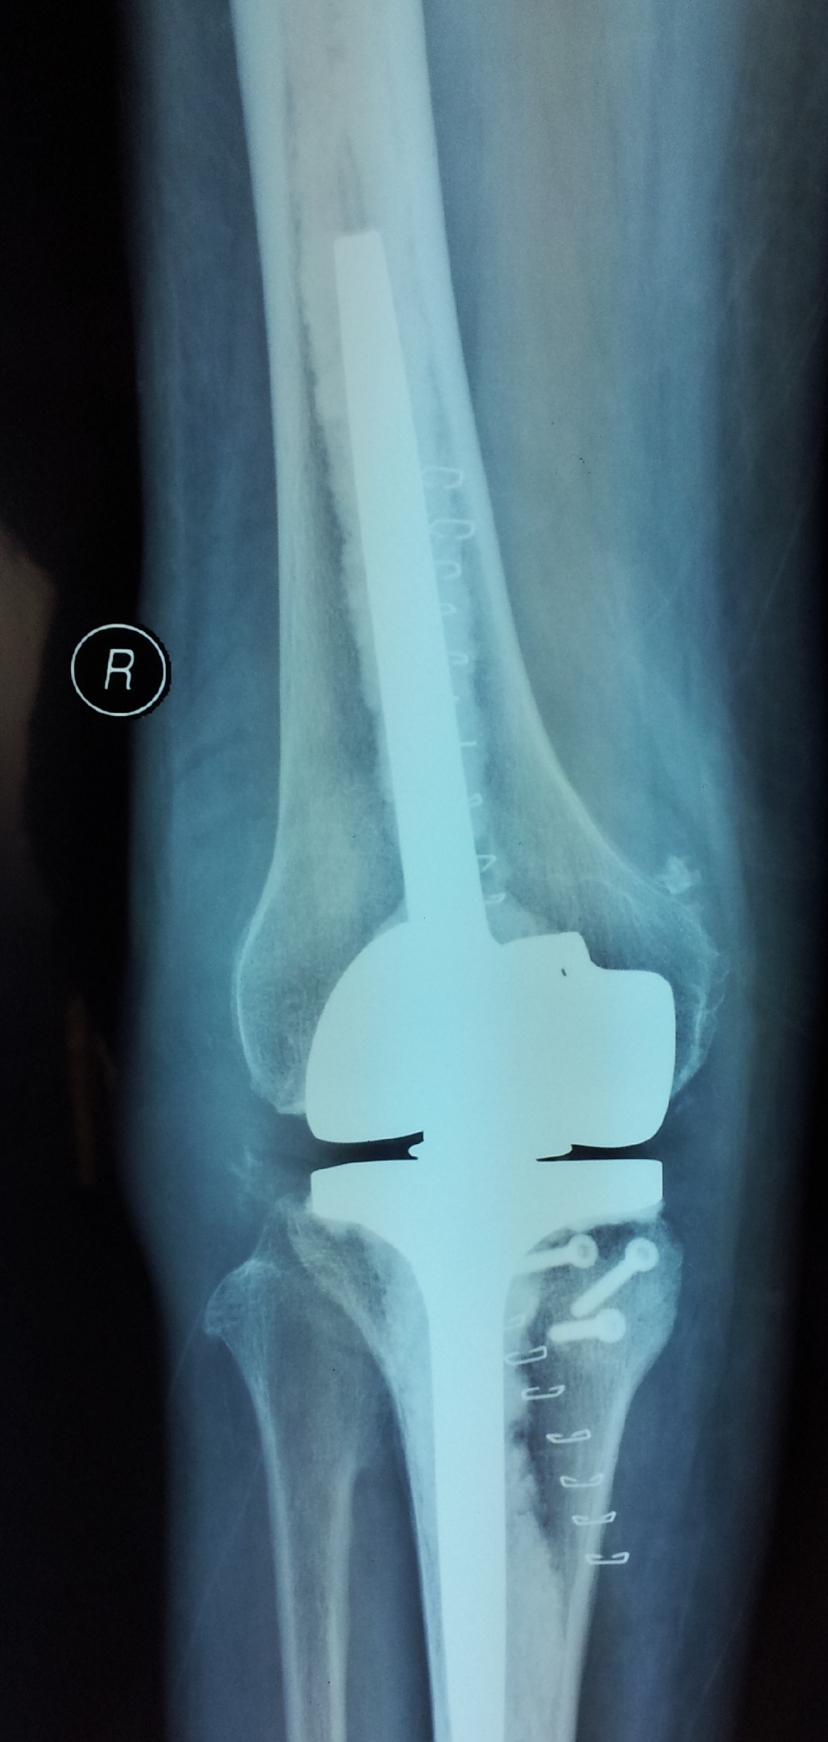

典型病例:患者,女,60岁,右膝骨性关节炎(重度内翻畸形)

术前                           术后

术前 正位                    术后正位